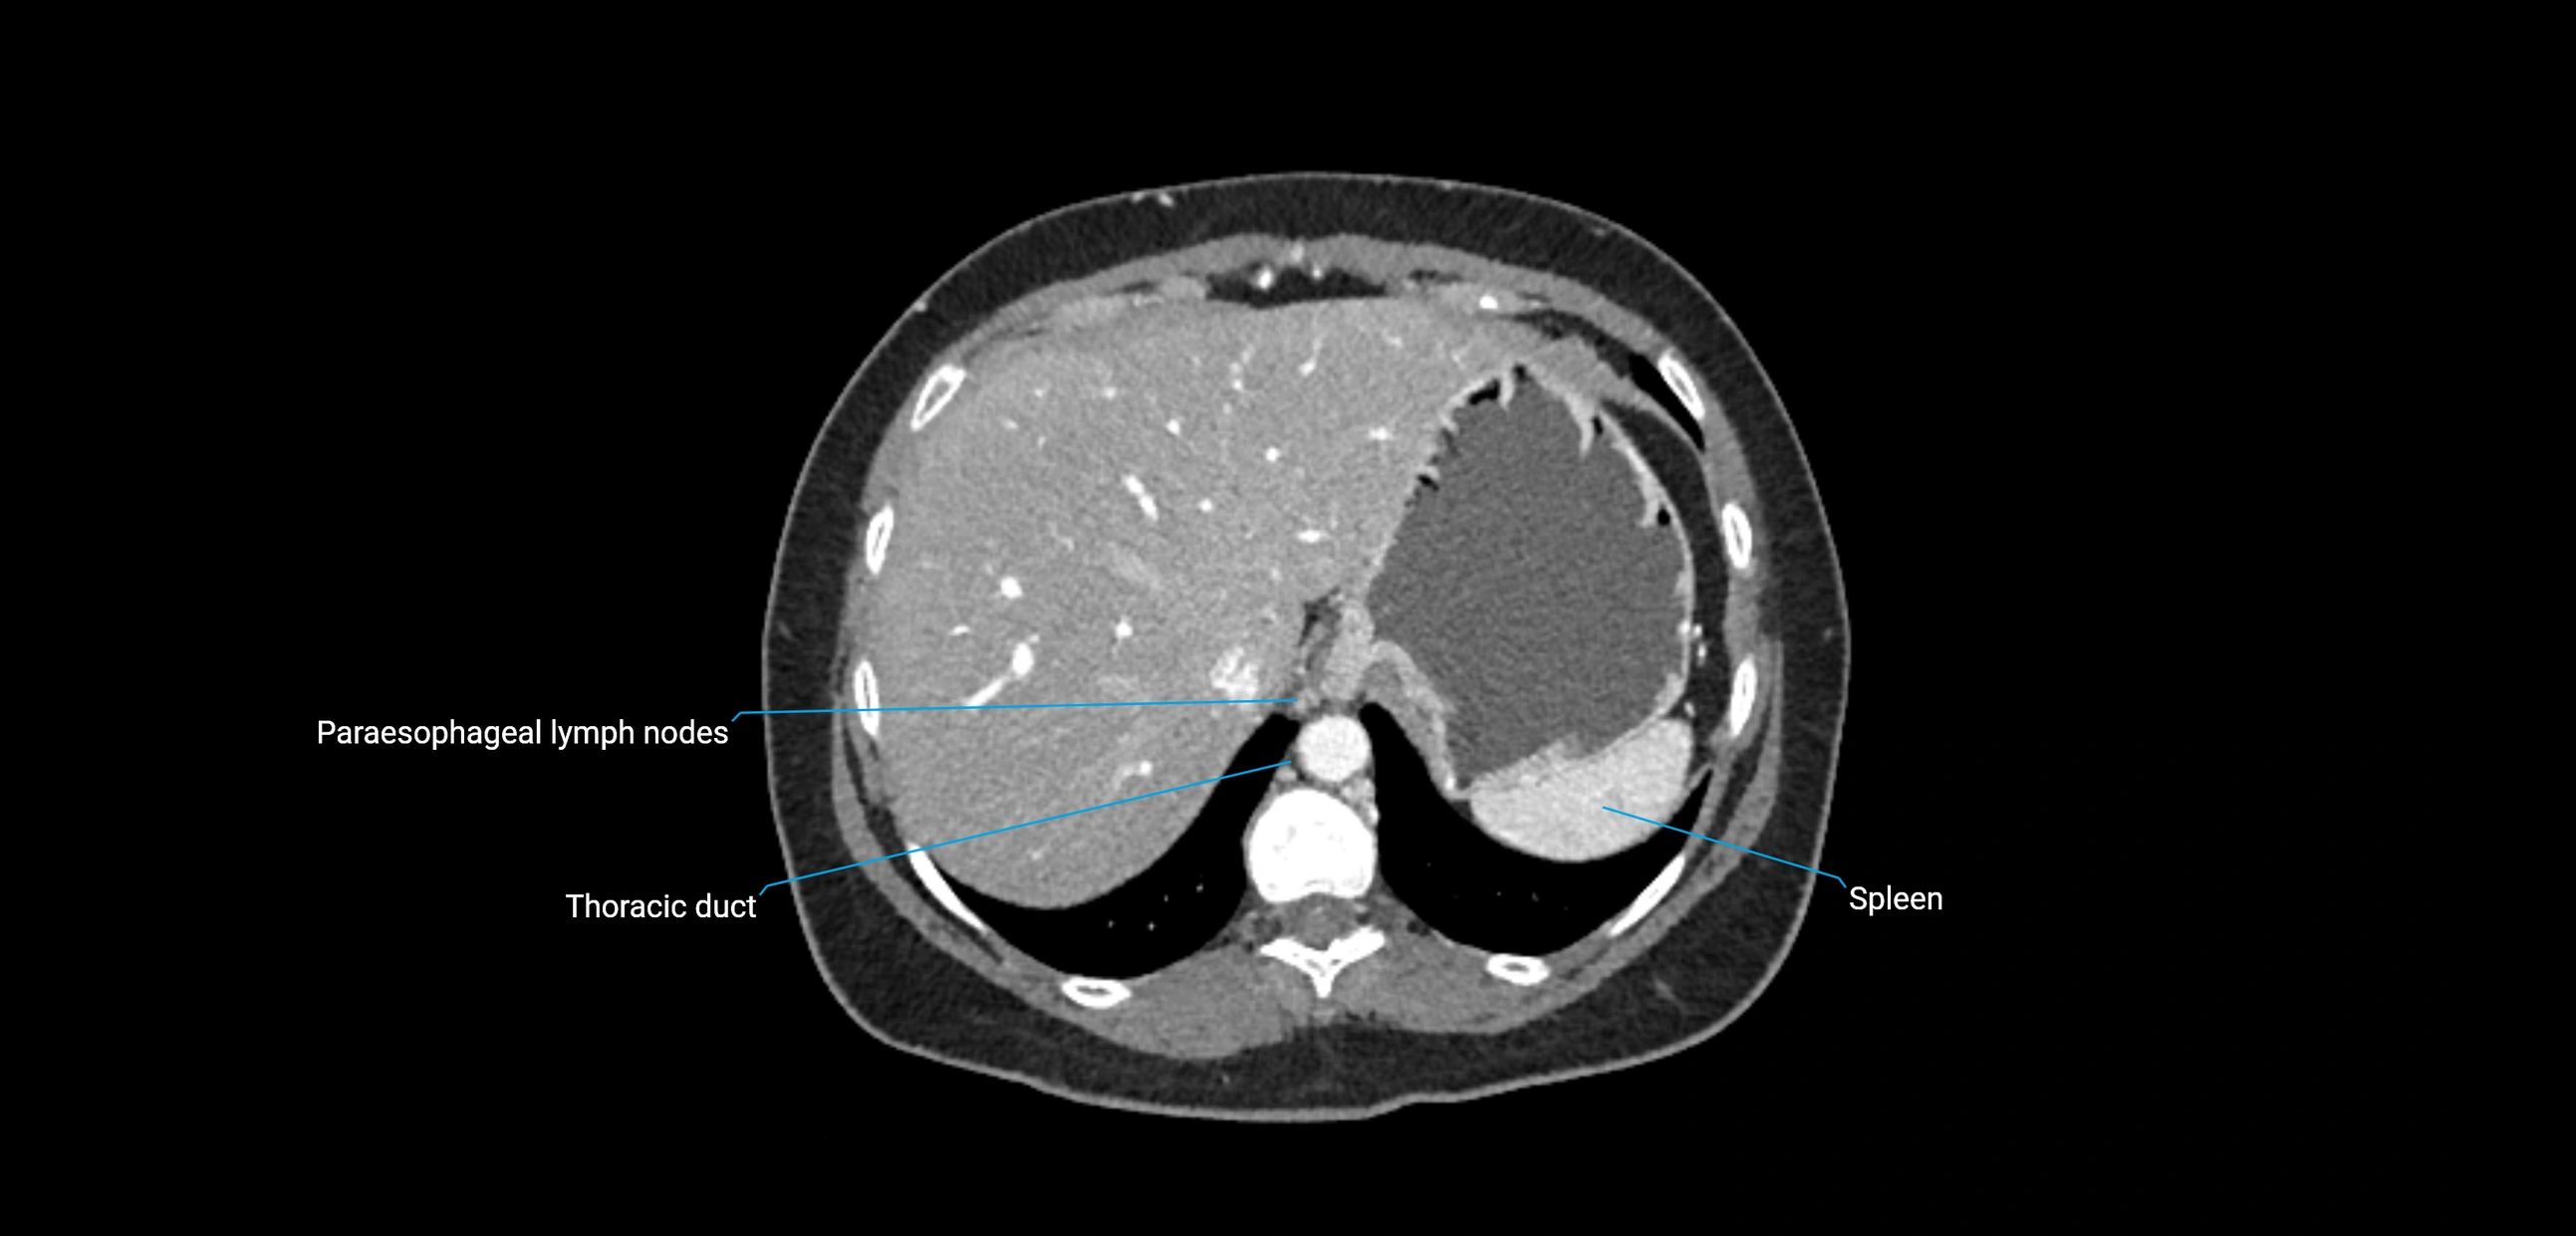

CT Appearance

CT Post-Contrast:

• Normal nodes enhance homogeneously

• Malignant nodes may show heterogeneous enhancement, central necrosis, or conglomerate formation

• Size >1 cm short axis is suspicious, though morphology and distribution are equally important

CT Venography (CTV):

• Demonstrates nodal encasement or compression of adjacent vessels (aorta, IVC, renal veins)

• Useful in staging testicular and ovarian malignancies